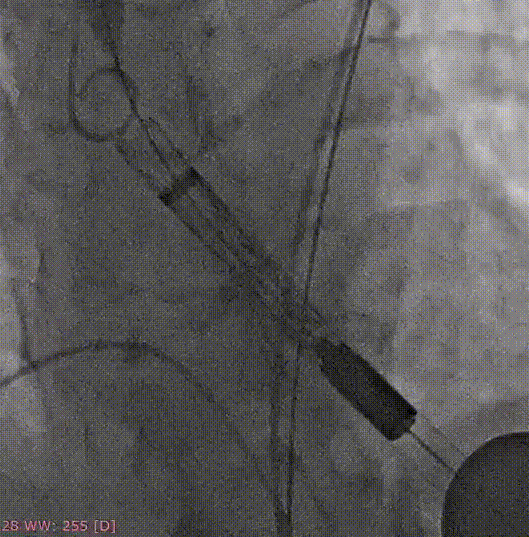

手术关键步骤

A.主动脉根部造影

B. 不前扩,输送系统一步到位

C. 应用交界贴合技术调整人工瓣膜,到安全梢固定位置,定位好,不需要回收,直接释放

D. 瓣膜释放后造影

E.球囊后扩

F. 最终造影